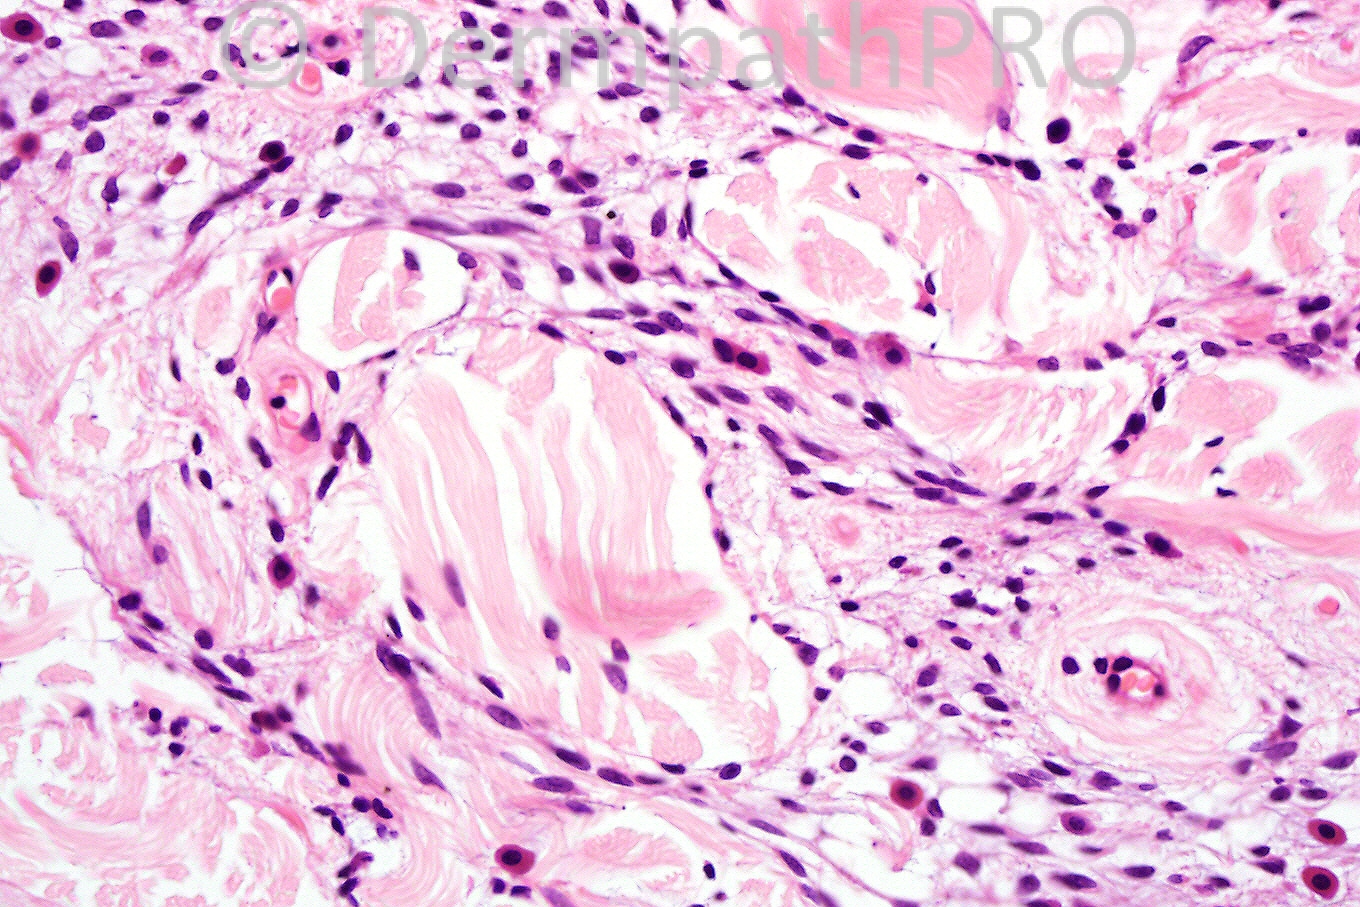

Male 62 years small tumor on shoulder.

The main features are the spindled cell population and the ropey collagen. The hyperchromatic giant cells are also a diagnostic clue. Given the clinical history, pleomorphic lipoma is the best diagnosis. Often with aging, the adipocytic component diminishes although it was present elsewhere in this specimen. Well done Marie.

Forgot to include spindle cell lipoma in my differential diagnosis. The lesion has classical ropey collagen with abundant mast cells. The age and site are also correct.

pleomorphic/spindle cell lipoma (adipocyte poor)...also thought of gc angiofibroma/sft

difficult case, spindle cell tumor, probably neural. I see lots of mast cells, and in the last picture there is nuclear atypia. I favor to be Neurofibroma.

I was wondering about ancient schwannoma or neurofibroma to explain the rather bizarre atypia, abundant mast cells, and rather sclerotic collagen. Meningothelial hamartoma also crossed my mind.